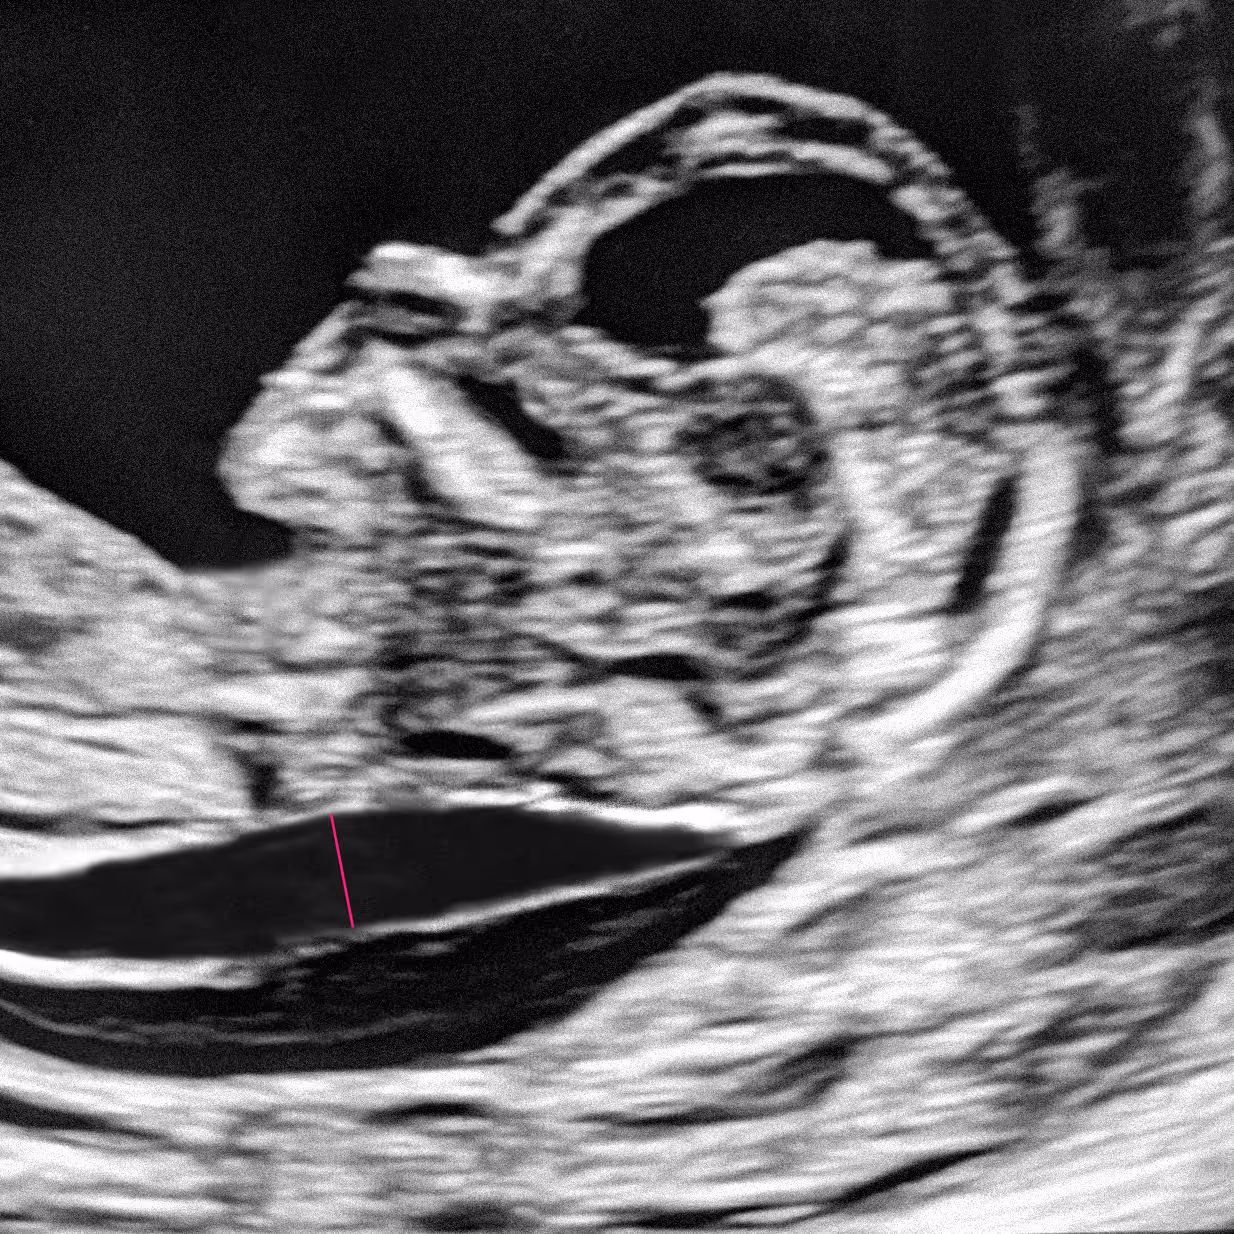

Peut-on connaître le sexe du foetus lors de la clarté nucale? Parfois oui, mais avec prudence!

L'échographie de suivi folliculaire surveille l'ovulation lors d'un traitement de fertilité.

L'échographie du bilan de réserve ovarienne évalue votre fertilité en comptant les follicules.

L'échographie de datation en début de grossesse confirme l'âge gestationnel et la viabilité.